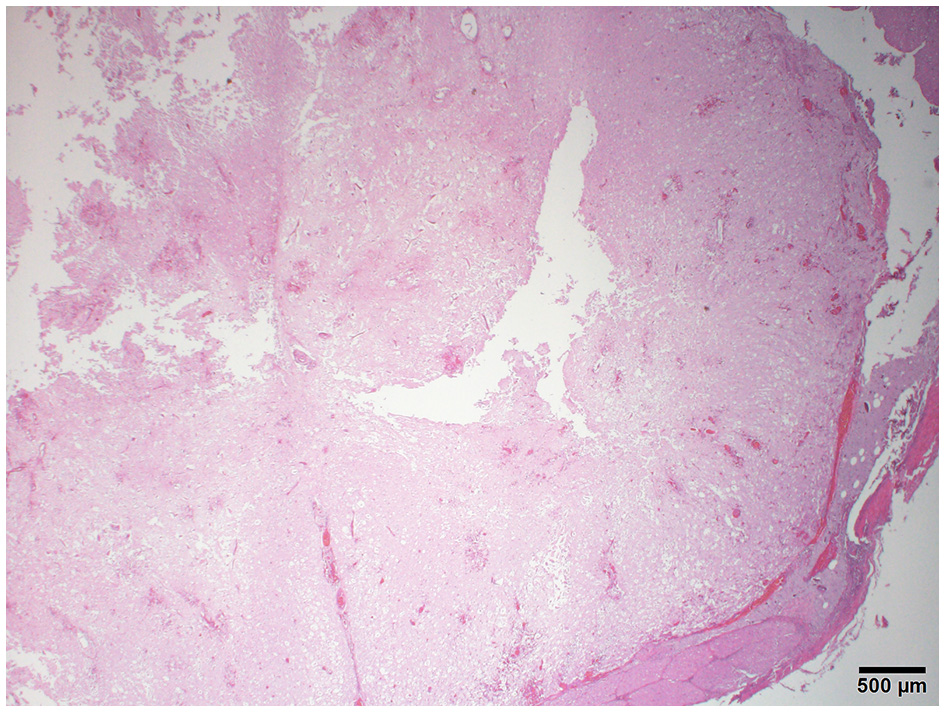

Figure 3

Photomicrograph of the cervical spinal cord with multifocal hemorrhage, severe tissue loss, cavitation, and lack of distinction between the gray and white matter. H&E stain.

The histopathology of her spine showed changes proximal to IVDE sites and was supportive of hemorrhagic progressive myelomalacia. The spinal cord had a loss of distinction between the white and gray matter. This was attributed to acute necrosis, multifocal to coalescing hemorrhage, loss of tissue with occasional cavitation, and mild neutrophilic inflammation (Figure 3). Within and around areas of necrosis, multiple thin-walled vessels were lined with decreased numbers of reactive endothelial cells and had fibrinoid vascular necrosis. In some less severely affected spinal sections, the residual white matter was often comprised of multiple swollen axon sheaths containing swollen hypereosinophilic and glassy axons (spheroids) and rare macrophages (digestion chambers) or was empty from axonal dropout (Figure 4). Histopathology of the brain had mild perivascular cuffs of lymphocytes, plasma cells, and rare macrophages in the meninges and choroid plexus consistent with mild inflammation.